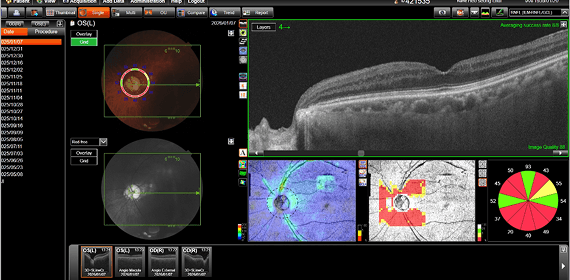

수술 전후의 객관적인 검사 결과를 통해

강남도쿄안과의 정교한 진료를 직접 확인해 보세요.